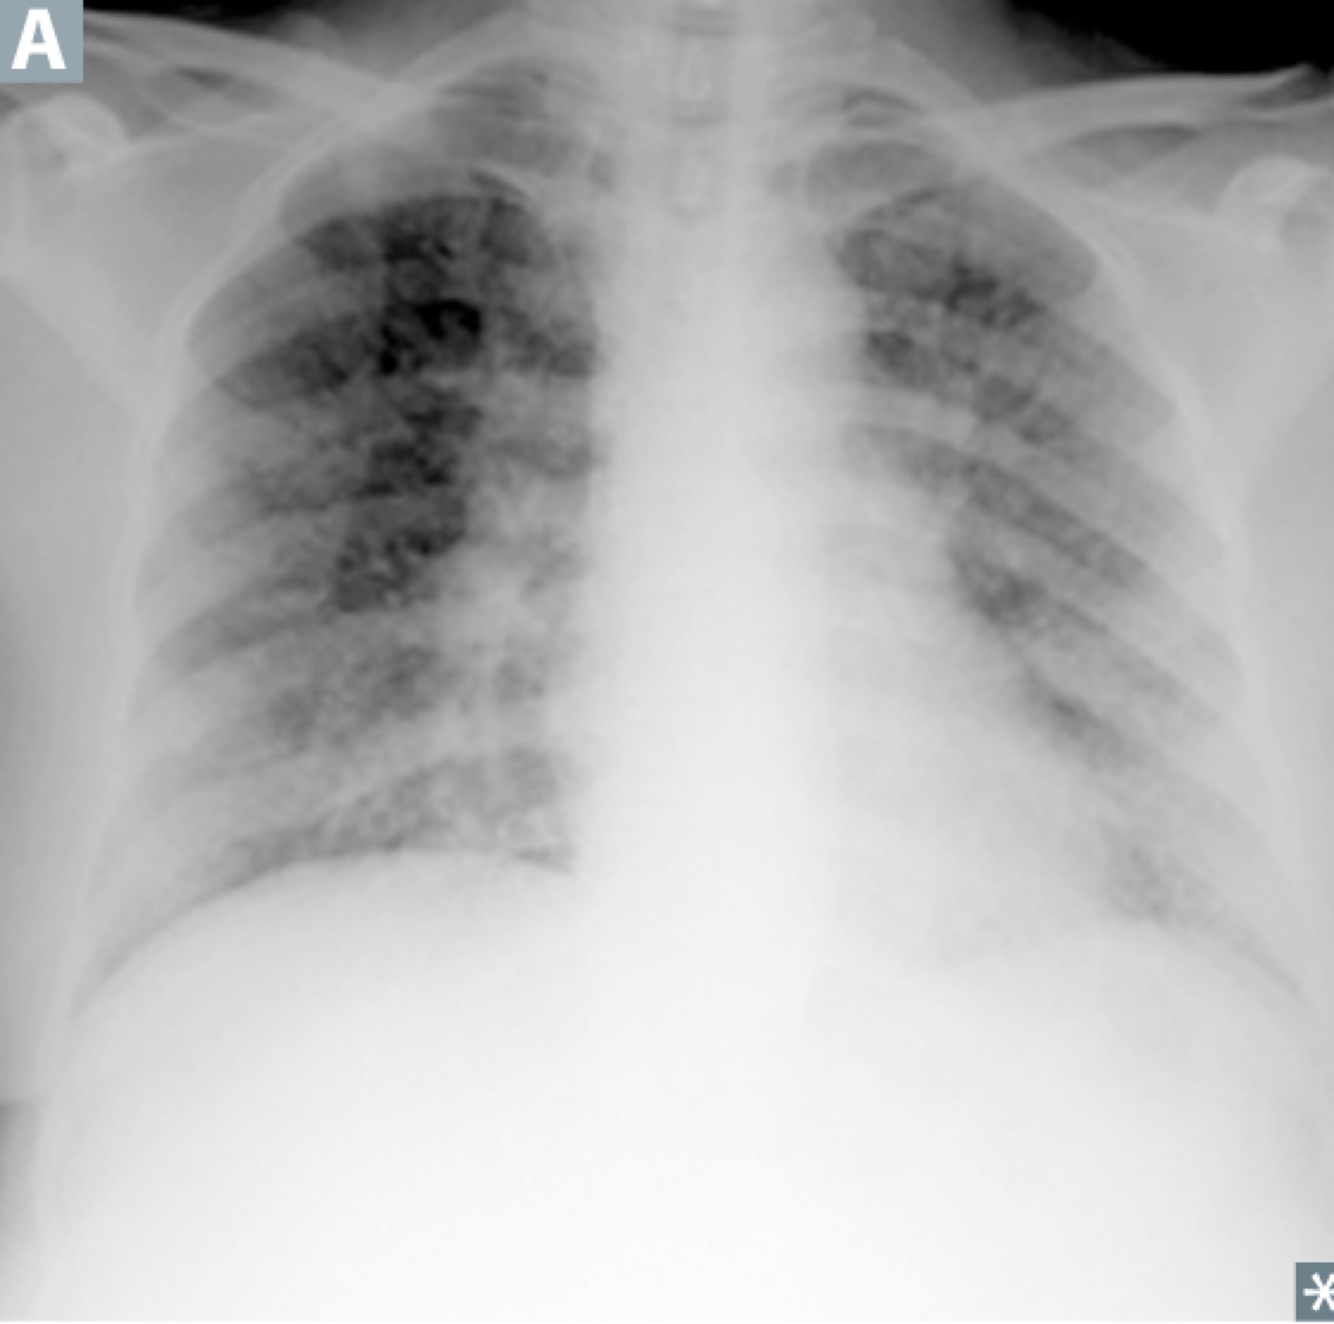

Pulmonary edema